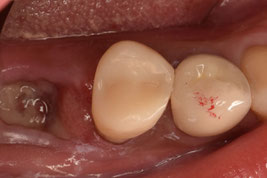

1回法で根管治療を終わらせてデンタルを撮影したところ、目を疑う光景がありました。

「6番の近心根がほぼそのまま残根しているぞ!…どうしよう」

根尖だけ若干残るのなら分かります。しかし、近心根がまるごと残っているのです。

患者さんに残根について説明し、限られたアポイントの中で、なんとか抜歯できました。